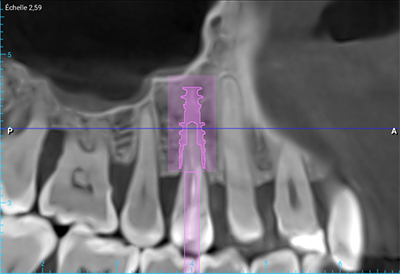

Fig. 03 : CBCT et planification implantaire (Nobel Active 3,5×13).

L’implant doit être placé de manière optimale dans les trois dimensions de l’espace :

• 3 à 4 mm en dessous de la gencive marginale vestibulaire ou de la jonction émail-cément des dents adjacentes ;

• 2 à 3 mm des dents adjacentes dans le respect de l’espace biologique péri-implantaire ;

• 3 à 4 mm à partir du rebord externe de la corticale vestibulaire créant ainsi un hiatus péri-implantaire.